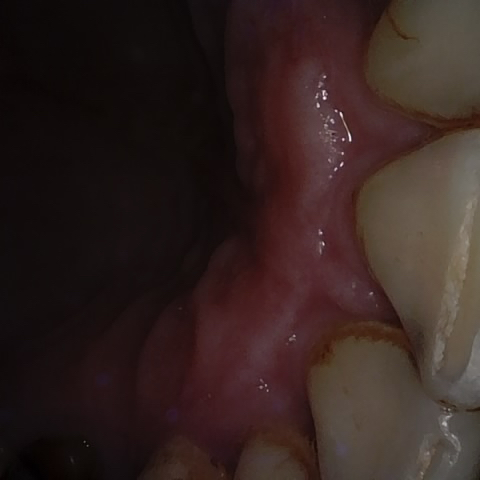

Annotated as "Good"